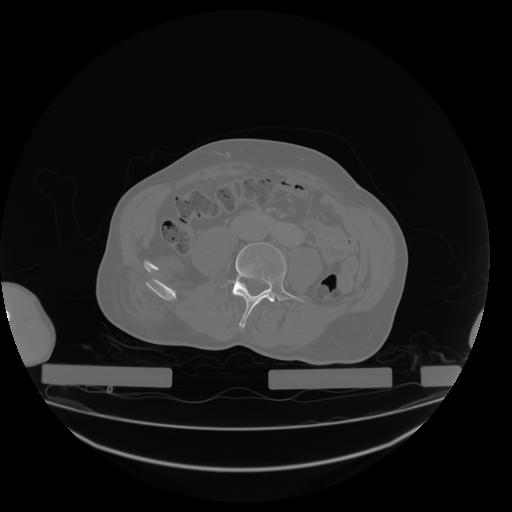

27 CUERPO,CE,Axial,3.0,CUERPO,,